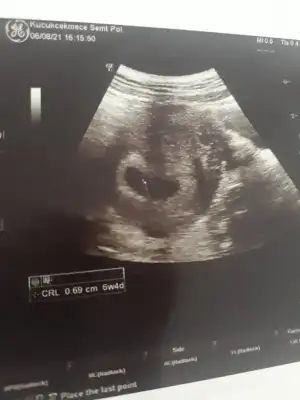

dr soylemeden siz gorun genital nub teorisi ( bebegin cinsiyeti)

Merhaba fotoğraf 10. Haftadan karın ultrasonu bakar mısınız?